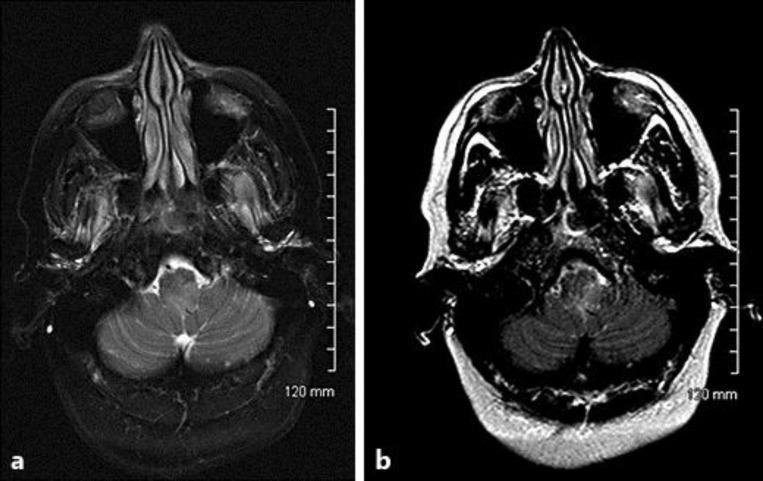

Primitive neuroectodermal tumors (PNETs) are typically present as masses in children and adolescents, but rarely in adults. Diagnoses, management strategies, and prognostication factors are not well established in adult cases of PNETs. We describe the case of a central nervous system PNET diagnosed in a 55-year-old woman presenting with a sudden onset of symptoms consisting of increased intracranial pressure and findings of diffuse leptomeningeal enhancement and a small medullary lesion seen on MRI. Amongst the small database of PNETs diagnosed in adults, our case report stands out as one of few cases describing a primarily leptomeningeal PNET diagnosed on biopsy. We also review the literature on PNETs presenting with diffuse leptomeningeal disease and the treatment of PNETs in the adult population.

原始神经外胚层肿瘤(PNETs)通常表现为儿童和青少年的肿块,但在成人中很少见。成人PNETs病例的诊断、管理策略和预后因素尚未明确。我们描述了一例在一名55岁女性中诊断出的中枢神经系统PNET,该患者突然出现症状,包括颅内压升高,MRI显示弥漫性软脑膜强化和一个小的髓内病变。在已诊断的成人PNETs小数据库中,我们的病例报告是少数描述经活检诊断为主要软脑膜PNET的病例之一。我们还回顾了关于表现为弥漫性软脑膜疾病的PNETs以及成人PNETs治疗的文献。